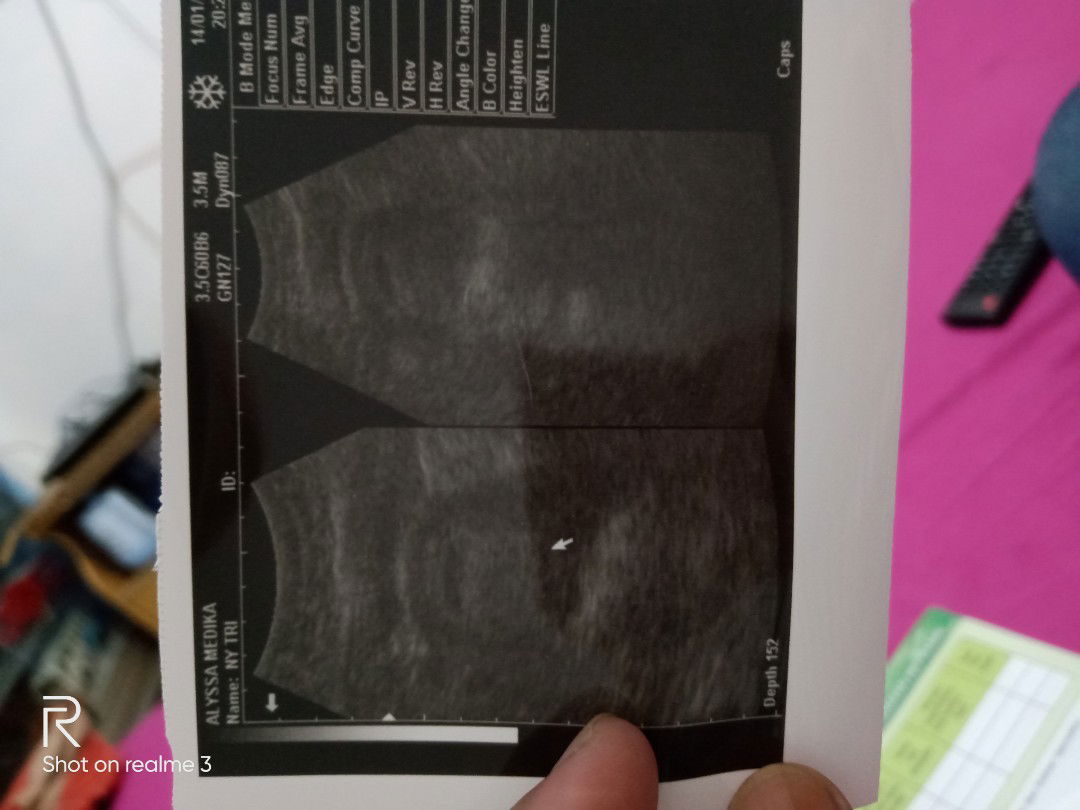

Belom keliatan ...???

Coba USG transvegina